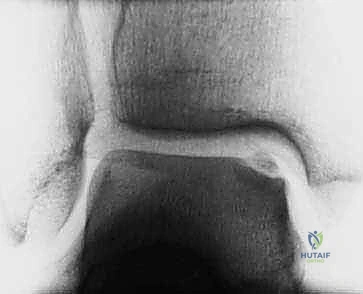

We use the Dipaola et al. MRI classification, based on Berndt and Harty's original radiographic system, to stage the lesion:

* Stage I: Thickening of articular cartilage and low signal changes.

* Stage II: Articular cartilage breached, low-signal rim behind the fragment indicating fibrous attachment.

* Stage III: Articular cartilage breached, high-signal changes behind the fragment indicating synovial fluid between the fragment and underlying subchondral bone. (This is what we see in our current case.)

*

* FIG 3 • Sagittal MRI (T2-SE-2000/90) showing an osteochondral lesion stage III.

* Stage IV: Loose body.